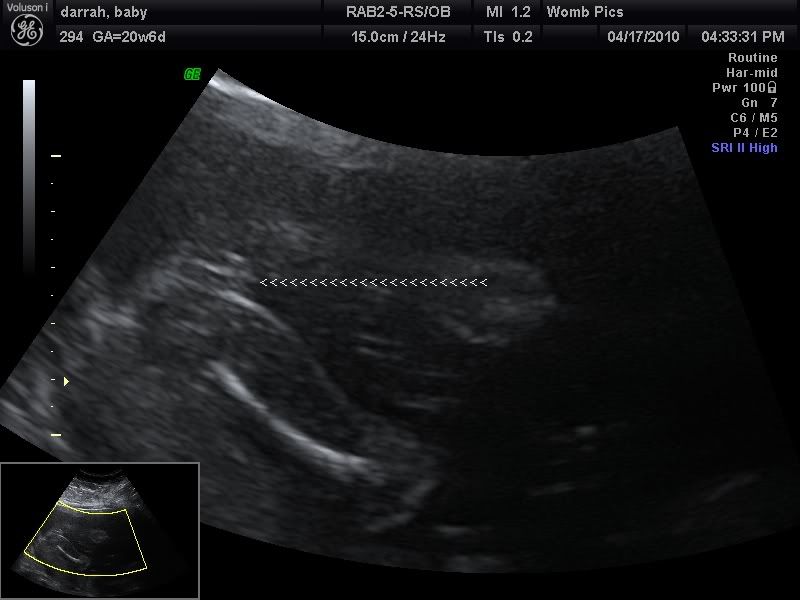

Call Me Crazy!!! w/ pic

Ok 2 different Techs said girl...but I see something btwn the babys legs lol.

I am scared I am going to go through what my cousin went through where they said girl then later said boy.

For those who are having girls did her privates look like this?

Looks girly to me! Labia tends to be swollen...

and I think a penis would be more formed at this point!

DD, at 20wks

I am 21 weeks

defintely a girl, those 3 lines are unmistakable (sp)

Yeah, the last tech that I went to pointed out three lines between my legs...looks like what you have there! My 's parts look totally different than that!

At 21 weeks that's definately a girl. My 13w sono for my looks similar to that but there's no mistaking if you're that far along.